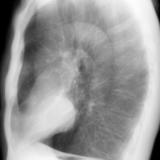

Case 1 Lat

Date: 03/17/2004

Views: 2840